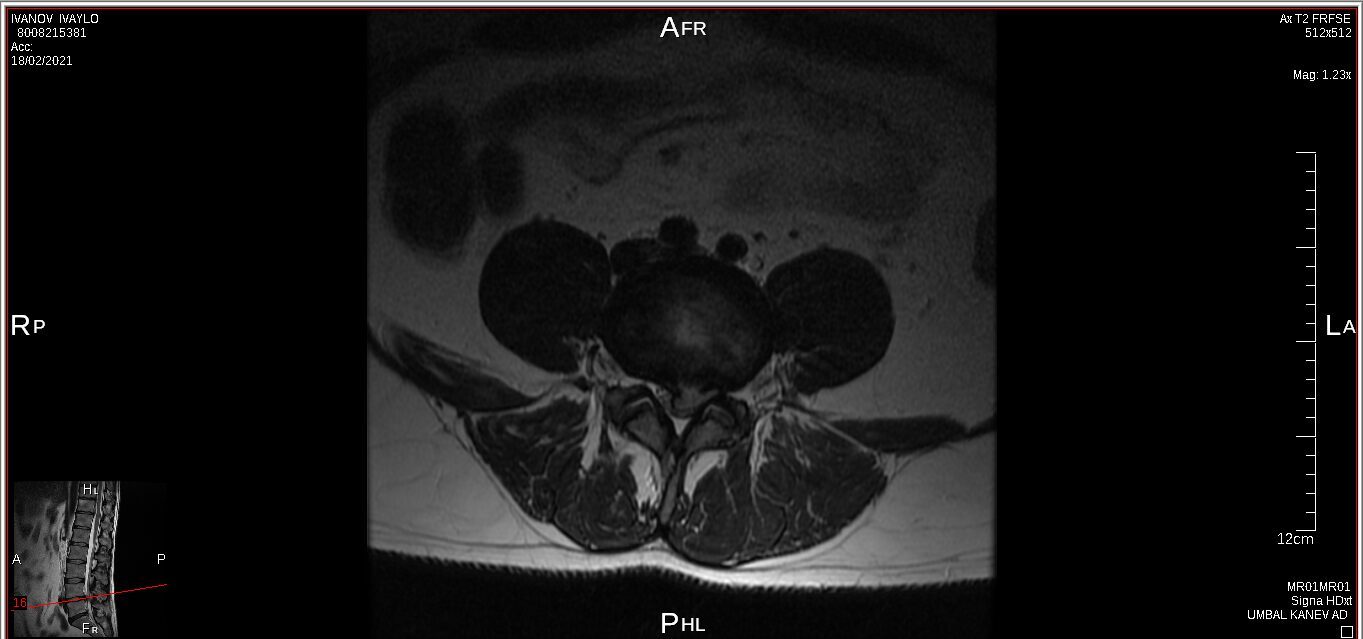

I have a lower spine problem, herniated disk and was using acupuncture (acupuncture is really good to control your musculus and controlling you like a robot) treatments with a Chinese doctor, first time all was perfect, but second time looks like happen mistake, you will be able to see this on pictures from private MRI scan– nuclear magnetic resonance that I have organised for myself. My left leg was just bone and skin, I lost all the musculus, because was not able to feed the main nerve responsible for keeping the proper function of the whole leg – I was parallelized. Pain is 24/7, 10 out of 10. At Royal infirmary hospital Edinburgh where I was hospitalized was giving me crazy amount of pain killers and very strong, that never helped. The doctors at the hospital they did great job providing me with modern technology to prevent the rest of the disk to slipping out to obtain the so-called calcification. All NHS staff did great job looking after me there. By 98% of the Doctors from around the world that I have managed to contact told me, that I have to make operation and there is no chance this to be sorted out other way. Well I have spent six months from my life and thanks god I had the finance to do that, trying to avoid operation. I have meet the right people to help me and expand my knowledge and I managed to avoid operation. Thanks to nature too. This situation get me to start learning a lot for human being anatomy and physiology, also reflexology, trigger points, blood, tocsins, minerals, how brain is responsible and reacting and much more…